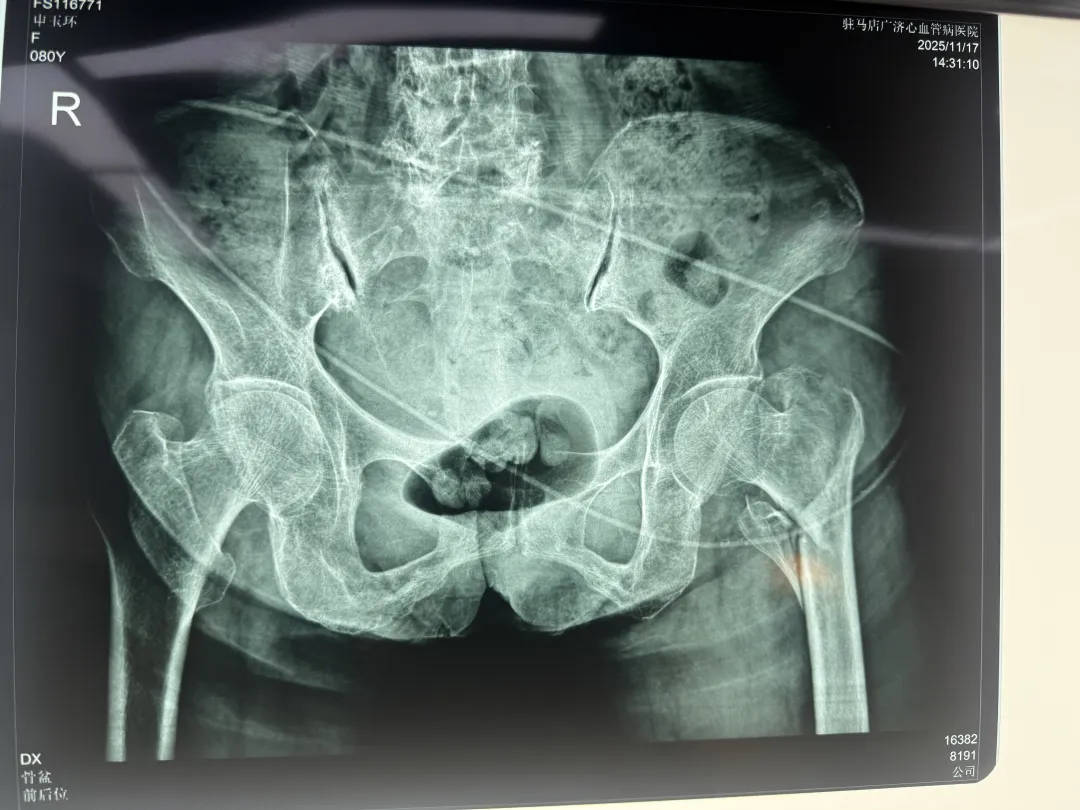

八旬高齡的阿婆在家喂狗時(shí)不慎滑倒,導(dǎo)致左髖部劇烈疼痛、無法活動(dòng)。經(jīng)檢查,診斷為“左側(cè)股骨轉(zhuǎn)子間粉碎性骨折”。對(duì)于高齡長者,這種骨折被稱為“人生最后一次骨折”,不僅死亡率增高,更意味著活動(dòng)能力和生活質(zhì)量的急劇下降,許多患者難以再回到受傷前的獨(dú)立狀態(tài)。

面對(duì)阿婆高齡、器官功能減退等高危因素,骨科團(tuán)隊(duì)高度重視,迅速組織病例討論。綜合考慮損傷類型與患者耐受性,團(tuán)隊(duì)最終決定為其實(shí)施“左側(cè)股骨轉(zhuǎn)子間骨折切開復(fù)位PFNA內(nèi)固定術(shù)”。